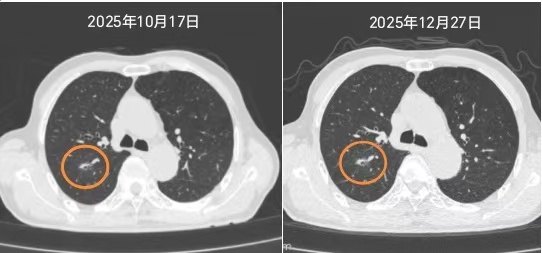

刚来到瑞金太仓分院的老陈,本想着治疗肝血管瘤,没曾想,术前一项常规的胸部CT检查,带来了意想不到的异常结果:普外科李勤裕主任医师仔细阅片后发现,老陈右肺上叶后段一枚亚实性结节很危险,当即邀请胸外科进行紧急会诊。陈凯医生仔细询问病史后,得知这个结节是首次发现,老陈平常也没有咳嗽、胸闷等不适症状,但结合影像学特征,临床高度怀疑为早期肺癌。为了优先处置恶性病变,医疗团队综合评估后决定暂缓肝血管瘤手术,优先处理肺结节,并制定了先抗炎治疗、短期随访以排除炎症的诊疗方案。两个月后,老陈如约来到陈凯医生的门诊复查,发现肺部结节仍然持续存在,肺癌的可能性进一步升高。